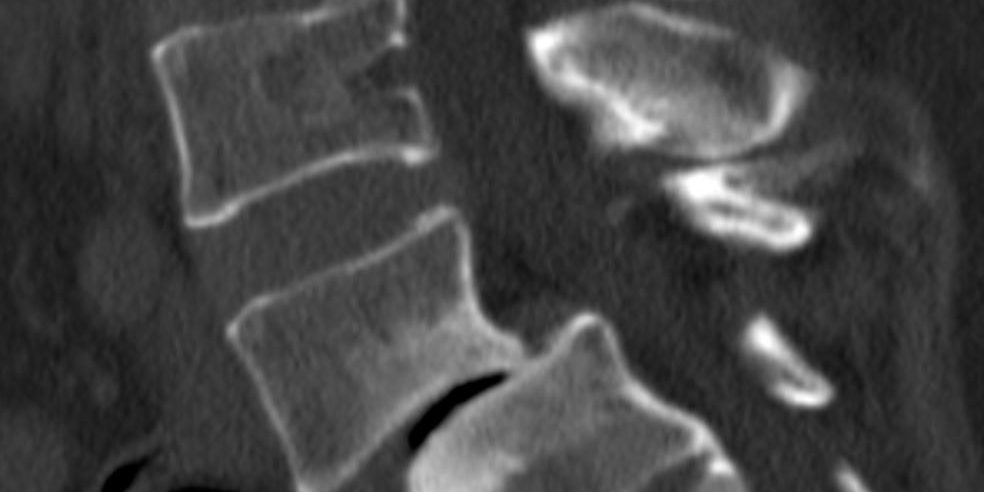

Ο απεικονιστικός έλεγχος ανέδειξε σπονδυλολίσθηση 2ου βαθμού σε έδαφος σπονδυλόλυσης (λύση της συνέχειας του οστού στον ισθμό, δηλαδή μεταξύ των δύο αρθρώσεων).